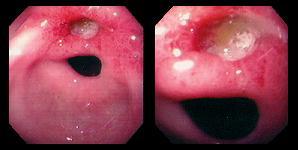

內視鏡下的胃潰瘍